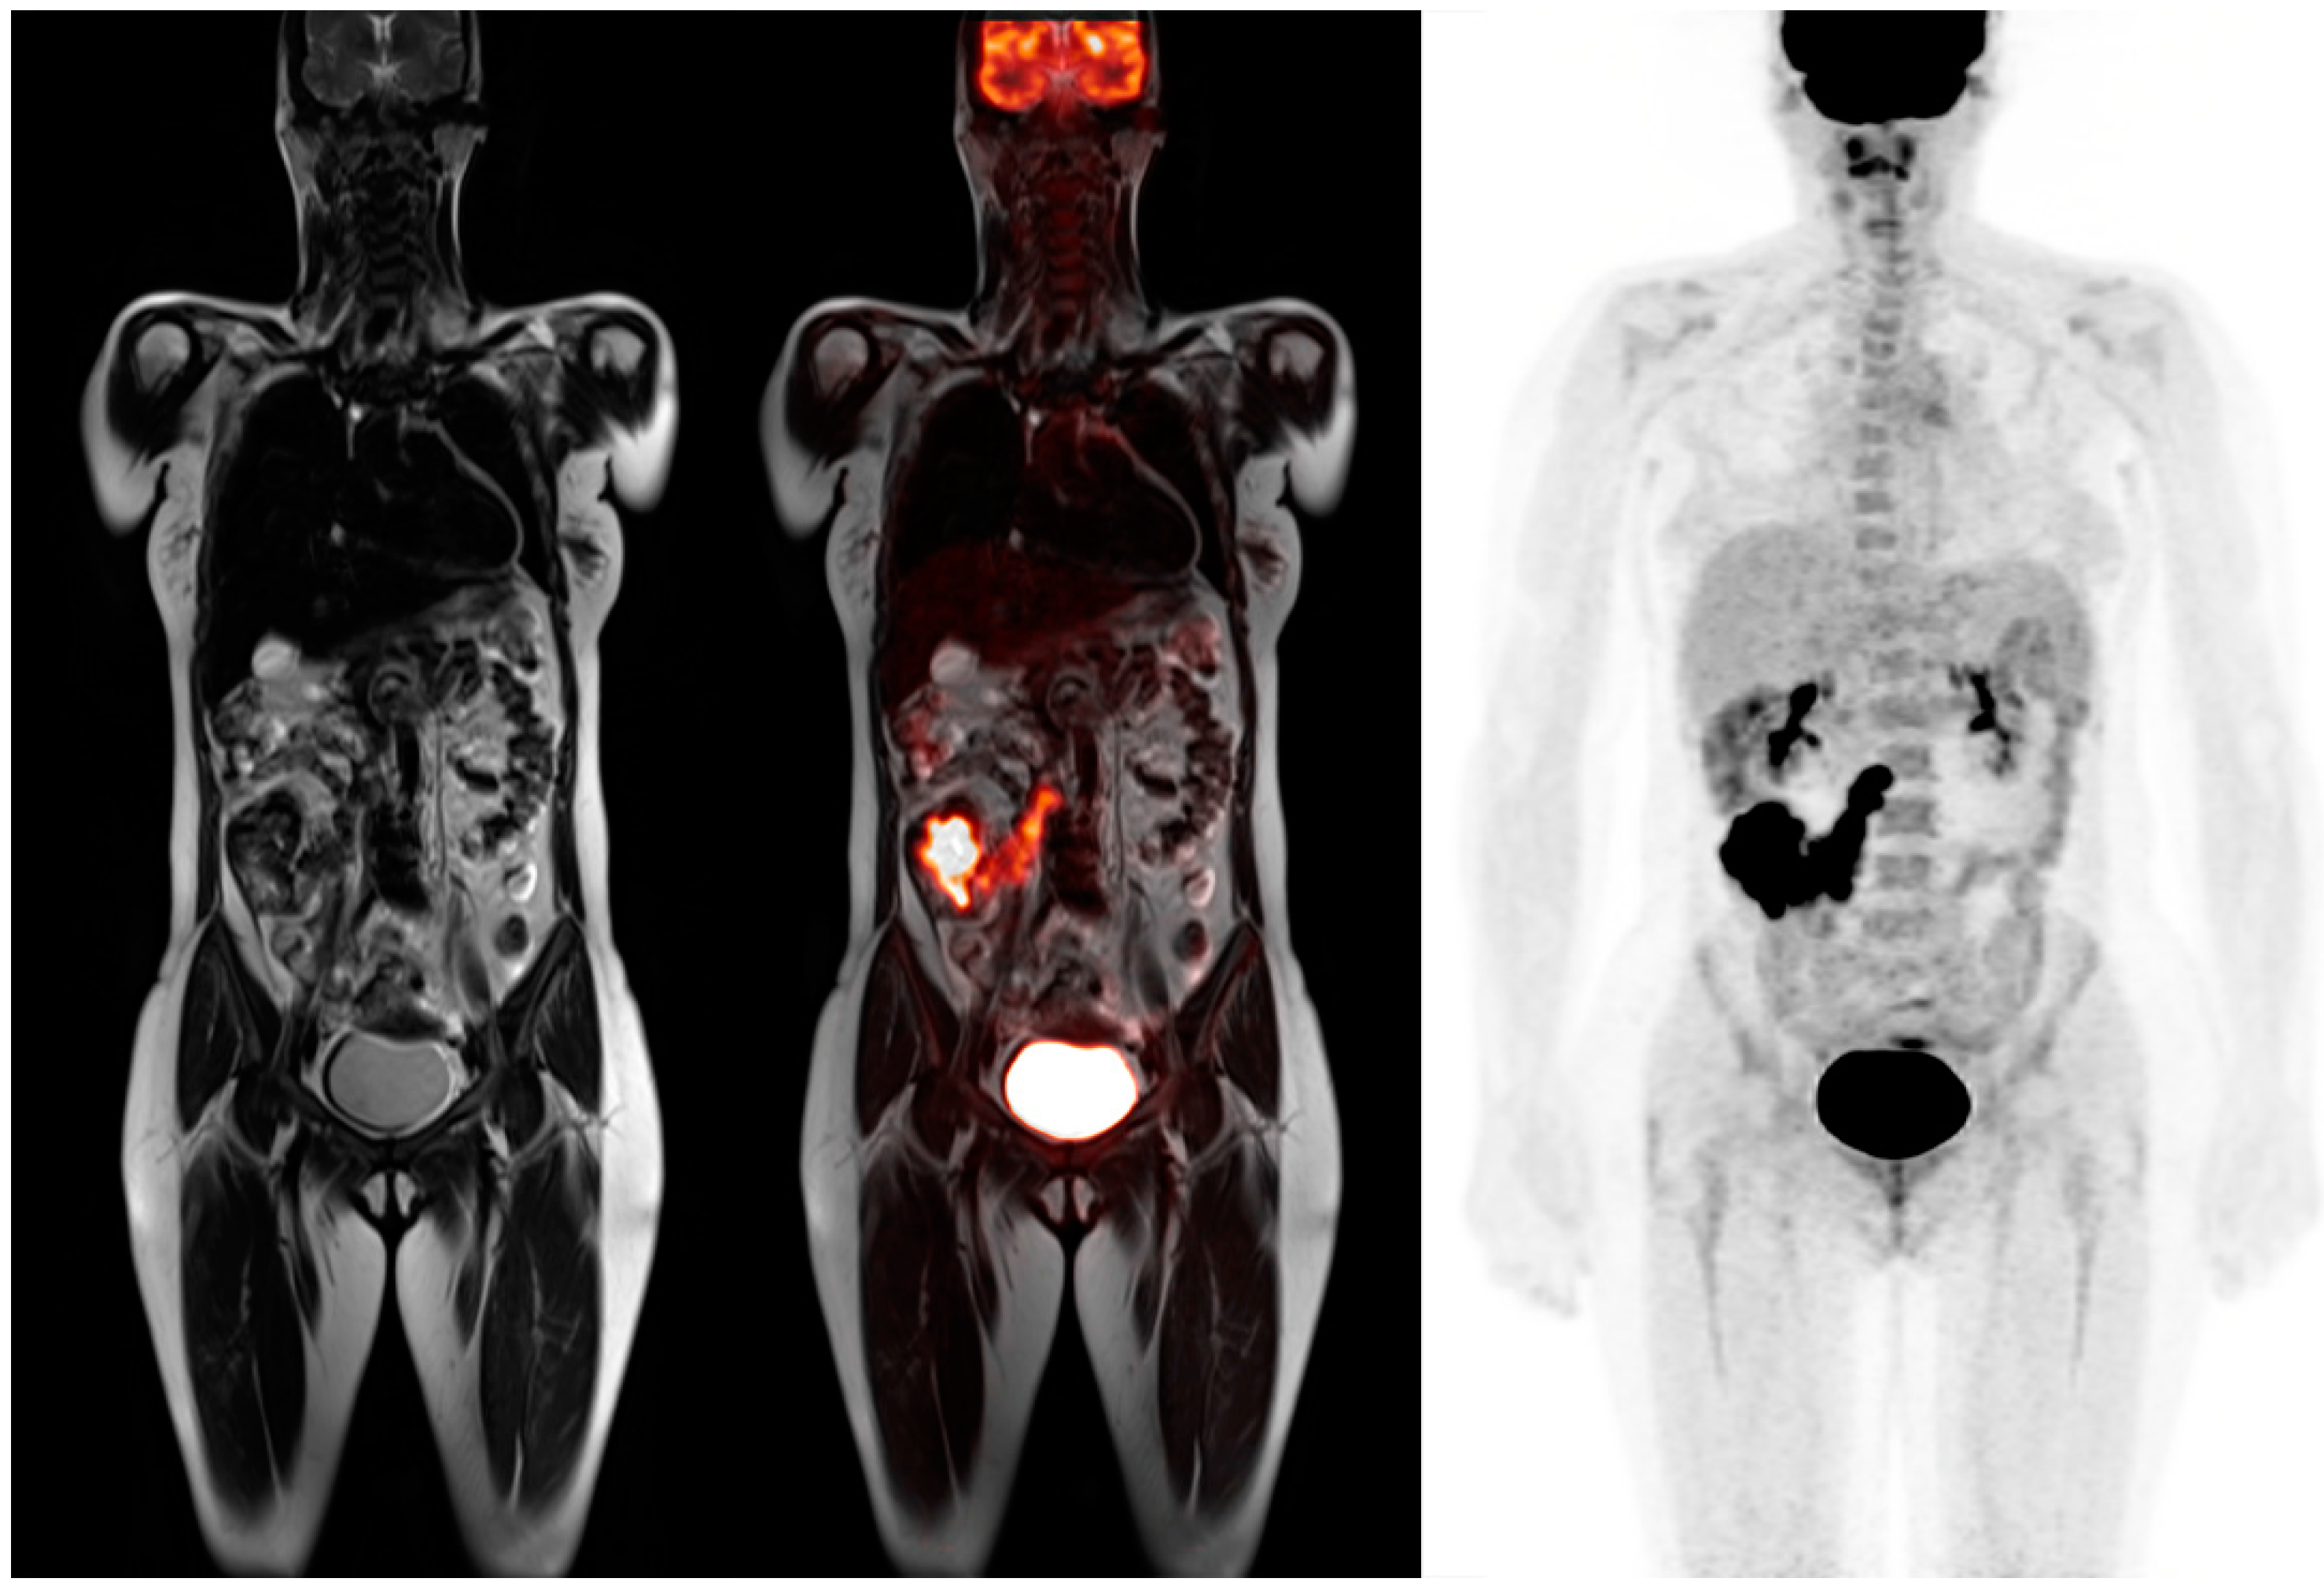

Unenhanced standard MRI sequences including T1 and T2 weighted images can accurately characterize and detect most focal liver lesions and can differentiate between solid and non-solid lesions as shown in Figure 3. Colorectal liver metastases are usually hypovascular, and therefore do not demonstrate significant enhancement with gadolinium based contrast agents [29]. MRI is more advantageous in the assessment of liver metastases when functional imaging like DWI and appropriate hepatobiliary contrast agents are used. Liver specific MRI contrast agents have the highest detection rate for focal lesions if the patient is being evaluated for curative surgical resection [30]. Kang et al. showed that PET-MRI added value to CT scan in 51 patients with colorectal cancer and led to 21% of patient changing therapeutic plans.

Figure 3.

72-year-old male with colon cancer. T1 precontrast transaxial image shows two low signal masses in segment 4B and 5 of the liver (top). T1 post contrast transaxial imaging with gadoxetate disodium reveals heterogenous enhancement of these two masses consistent with metastatic colon cancer (middle). PET-MRI transaxial fusion image confirms malignancy by demonstrating intense FDG activity (bottom). Also note the adjacent benign hemorrhagic cyst with high T1 signal that does not exhibit increased metabolic activity on the fusion images.

The risk of lymph node involvement increases with depth of tumor wall invasion ranging from 15% to 65%. Traditional mesenteric lymph node metastases are based on nodal size and shape with 5 mm being the optimal size. Both CT and MRI have detection capabilities for nodal metastases. However, reactive lymph nodes are common and can confuse interpretation of metastatic spread [31]. FDG PET-MRI has been shown to be useful in characterizing indeterminate lesions including borderline enlarged lymph nodes and small hepatic metastases. The absence or presence of FDG uptake in mesenteric lymph nodes leads to a more accurate assessment of local metastases as shown in Figure 4. In addition, PET-MRI can provide more detailed T staging than PET-CT alone with better characteristics of colorectal wall invasion [32,33].

Figure 4.

45-year-old female for initial staging of colon cancer. T2 coronal image shows a large right colon mass with multiple low signal intensity lymph nodes (left). PET-MRI coronal fusion images better reveal the colon mass and chain of mesenteric lymph nodes that extends to the paracaval region (middle). PET MIP image shows the prominent FDG activity in the colon cancer and lymph node metastases (right).